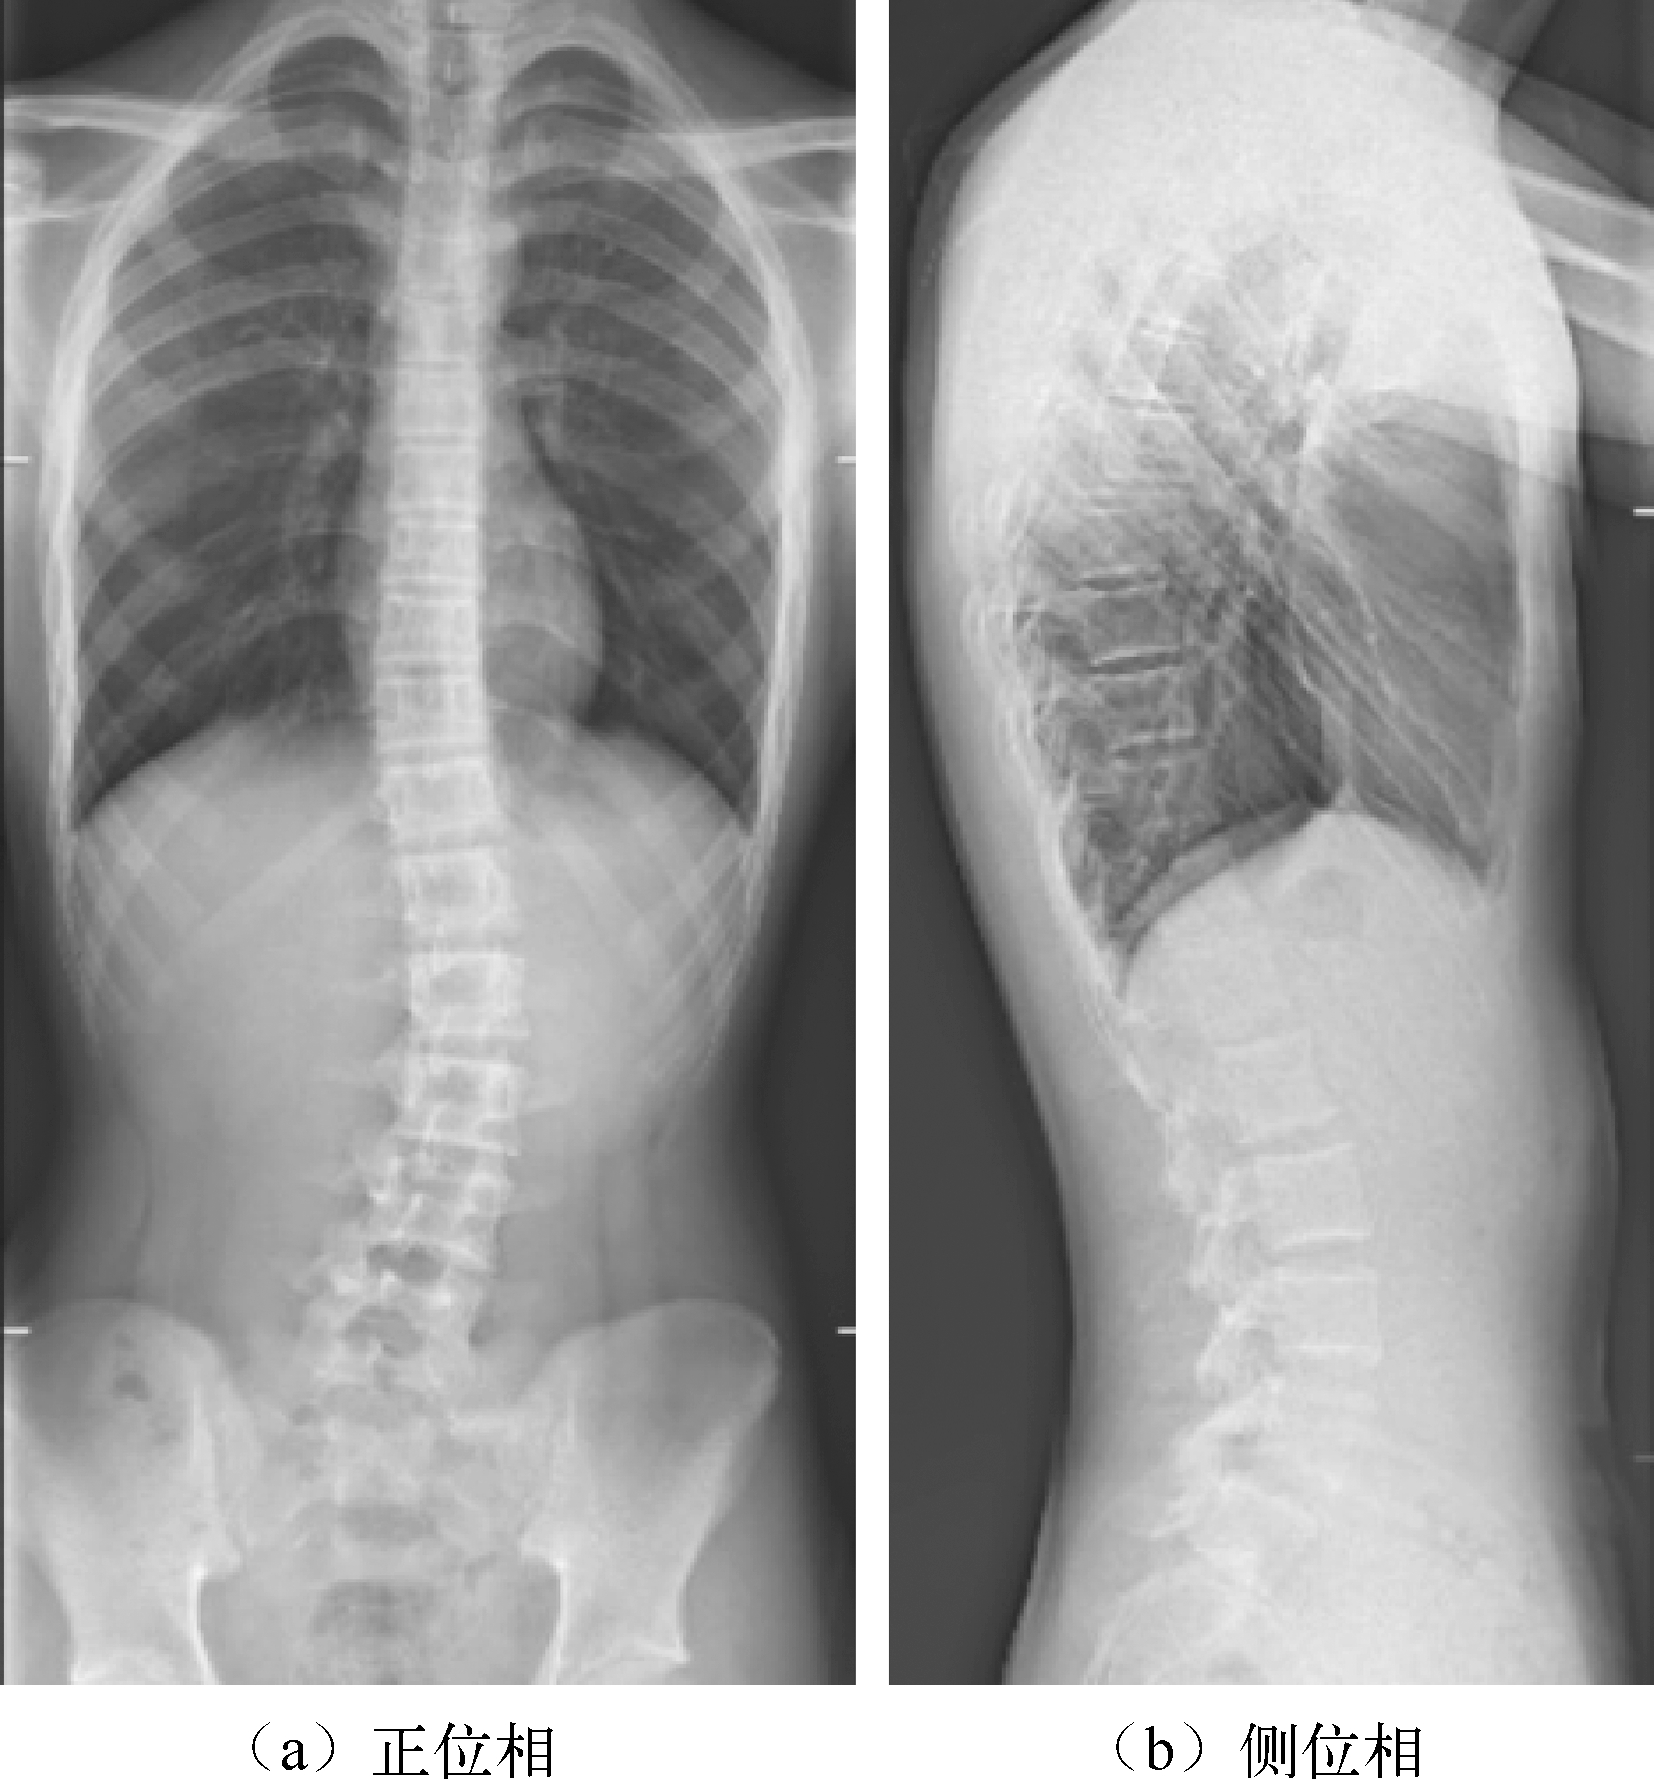

相比CT或MRI,X线成像设备费用较低,而且具有简便、快速和检查费用低等优点。脊柱侧凸的X线检查通常是对患者正、侧位成像,即获得冠状面和矢状面图像,如图1.7所示。相比CT,两幅X线成像的辐射伤害要小得多,而且能够在患者各种测试姿势下成像(直立、侧屈、前屈、坐立、仰卧等)。通常青少年患者需要每隔3~6个月复查,跟踪评价侧凸的发展,直到骨骼发育成熟。因此X线成像是目前诊断评估脊柱侧凸的首选成像模式。根据X线图像可以对侧凸的弯度、椎体旋转程度、骨骼发育程度、脊柱的柔韧性以及脊柱侧凸的分型进行评估 [1] 。但是,脊柱侧凸是三维空间的畸形,二维(2D)X线图像不能全面反映三维畸形特征,难以发现畸形在冠状面和矢状面以外的三维空间中的发展变化。医生更需要三维信息对侧凸进行更准确的诊断、治疗和治疗后评价。因此,如果能够通过常规二维X线图像获得三维脊柱形态,必将有助于医生的诊断和跟踪治疗。

图1.7 脊柱侧凸正位相和侧位相X线图像